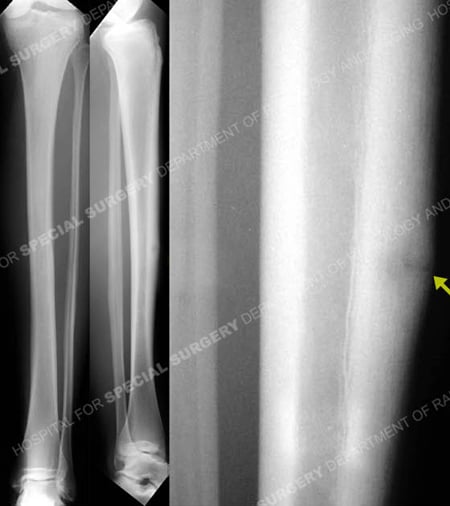

Mid-shaft Stress Fracture of the Anterior Tibial Cortex

A 19-year-old female Olympic pole vaulter presented to the Dr. David L. Helfet at the Orthopedic Trauma Service at Hospital Special Surgery with a 12-month history of right-sided tibia pain. Radiographs revealed a mid-shaft stress fracture of the anterior tibial cortex. After past unsuccessful initial treatment with rest and physiotherapy modalities (including ultrasound) for 5 months, she underwent anterior tension band plating with a locked LCP plate and unicortical and bicortical screws. Postoperative follow-up was uneventful and bony union was noted at 3 months postoperatively at which time she resumed her training regime. Two years after the operation, the patient complained of mild discomfort related to the plate, and the hardware was removed. At most recent date of follow up, 2 years post surgery, she is doing exceptionally well with resolution of pain and began training again for the United States Olympic team.

Anteroposterior and lateral radiographs reveal a stress fracture of the anterior tibial cortex.